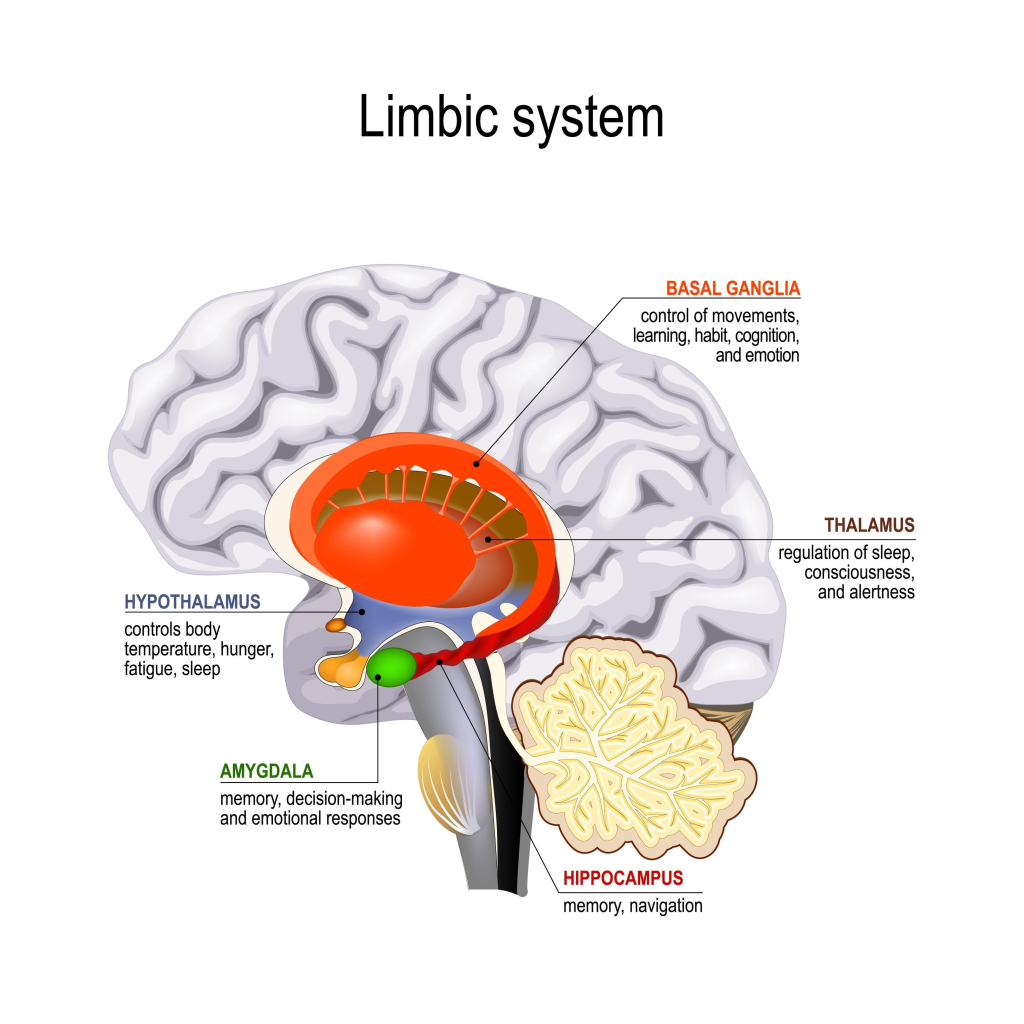

- Alt Beyin (İlkel Katman): Hayatta kalma, üreme ve anlık haz peşinde koşan Limbik Sistem. Tasavvufun “süfli arzular” dediği bölge burasıdır.

Nefs-i Emmare (Kötülüğü Emreden) ve Nefs-i Levvame (Kendini Kınayan) aşamaları, biyolojik olarak amigdala ve ödül mekanizmalarının hakimiyeti altındadır.

Emmare mertebesi, beynin Amigdala bölgesinin yönetimi ele geçirdiği bir “reaksiyon” halidir. Bu aşamada birey, mantıklı düşünmek yerine dürtüsel hareket eder.

- Dopaminerjik Bağımlılık: Bu safhadaki nefis, sürekli bir ödül peşindedir. Beynin ödül merkezi, her anlık hazda (öfke, aşırı tüketim, bencil arzular) dopamin salgılayarak kişiyi biyolojik bir haz döngüsüne hapseder.

- Kortizol ve Savunma: Amigdala aktif olduğunda irade merkezi (prefrontal korteks) devre dışı kalır. Tasavvuftaki “basiret bağlanması”, nörolojik olarak rasyonel beynin bu kararma halidir.

• Nefs-i Emmare (Dürtüsellik), şemada Pons ve Medulla’nın hemen üzerinde bulunan Amigdala (Limbik Sistem) ile ilişkilidir.